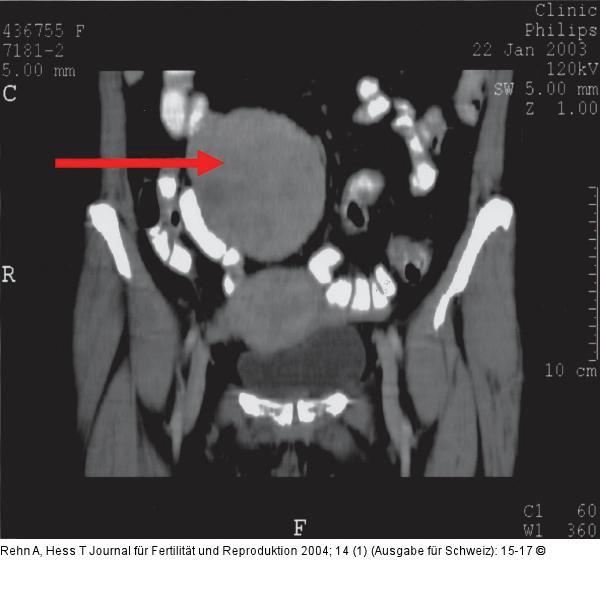

Abbildung 4: Leiomyomatöse Omentum majus-Neoplasie Fall 2: CT: Pfeil: Weichteiltumor fundal des Uterus im mesenterialen Fettgewebe gelegen. |

Abbildung 4: Leiomyomatöse Omentum majus-Neoplasie

Fall 2: CT: Pfeil: Weichteiltumor fundal des Uterus im mesenterialen Fettgewebe gelegen. |